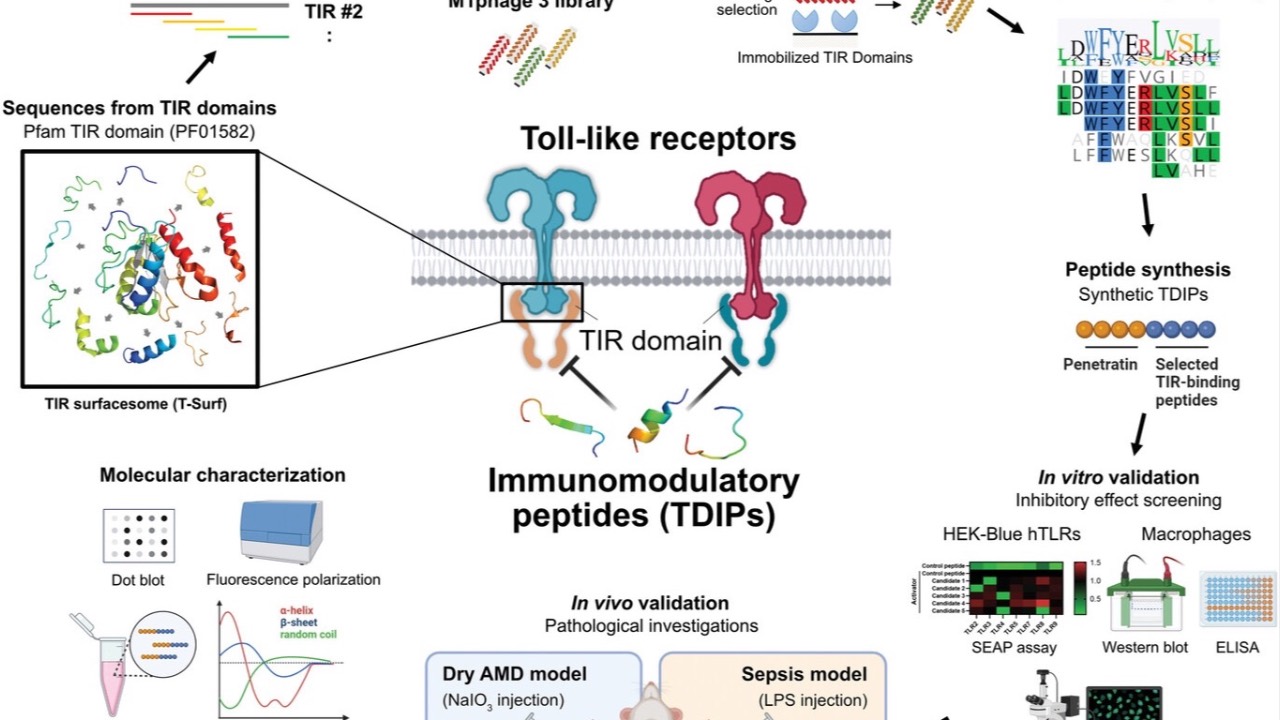

Topical Treatment For ARMD?

Eyedrops may be just on the horizon...

Toll-Like Receptors (TLRs) play a key role in retinal inflammation, and recently a brilliant study has pointed to the potential of TDIP (Toll/interleukin-1 receptor derived immunomodulatory peptides) eye drops in targeting and combating sodium iodate (NaIO3)...